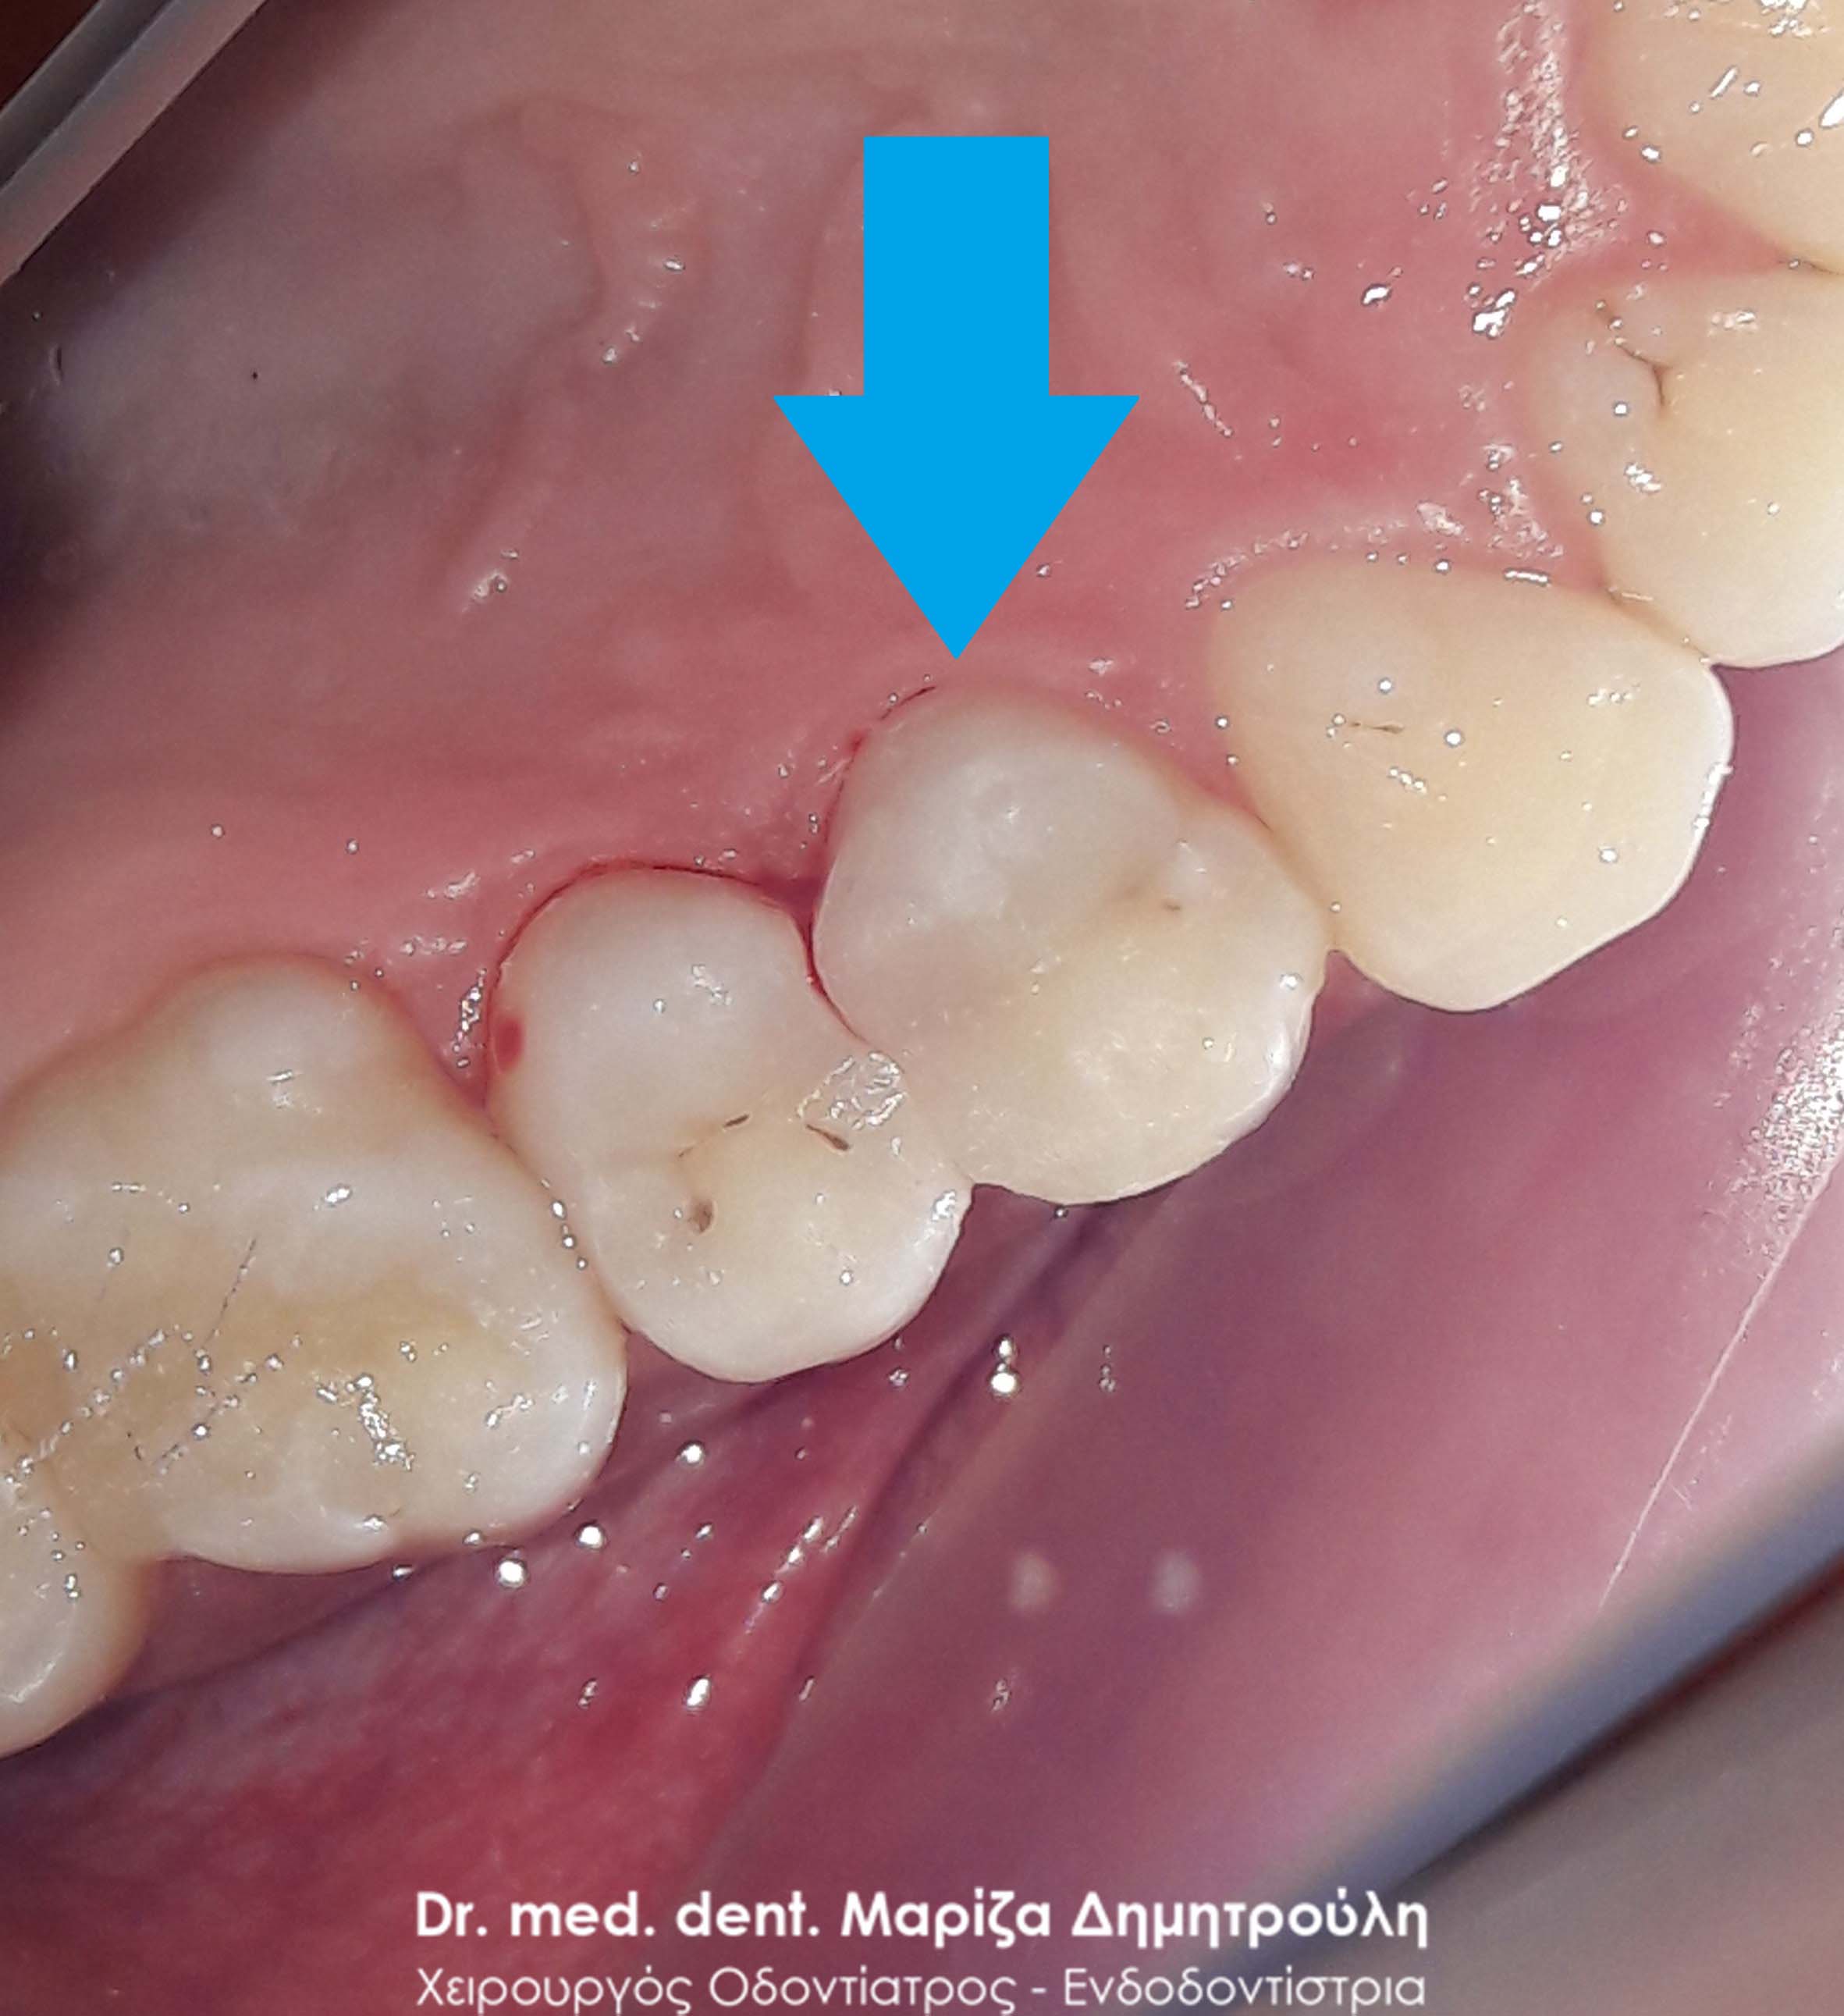

Στο παρόν περιστατικό απουσιάζει η αρχική εικόνα των δύο δοντιών πριν αρχίσει ο εκτροχισμός τους. Διαθέσιμες είναι μόνο η ενδιάμεση εικόνα που παρουσιάζει το εύρος του οδοντικού ελλείμματος στα δύο γομφίους της αριστερής πλευράς της άνω γνάθου και η τελική εικόνα αποκατάστασης των δύο δοντιών.

Η ασθενής αισθανόταν τις τελευταίες μέρες έναν ήπιο πόνο κατά τη μάσηση τροφών. Μετά την κλινική εξέταση του στόματος διαπιστώθηκε η ύπαρξη τερηδονικών κοιλοτήτων στους δύο άνω αριστερούς γομφίους. Αποφασίστηκε με τη συναίνεση της ασθενούς η αντικατάσταση των σφραγισμάτων. Στον πρώτο γομφίο διορθώθηκε μόνο η μισή έκταση του παλιού σφραγίσματος, καθώς κρίθηκε οτι δεν ήταν απαραίτητη η αφαίρεση ολόκληρου του παλιού σφραγίσματος.

ΠΡΙΝ

META